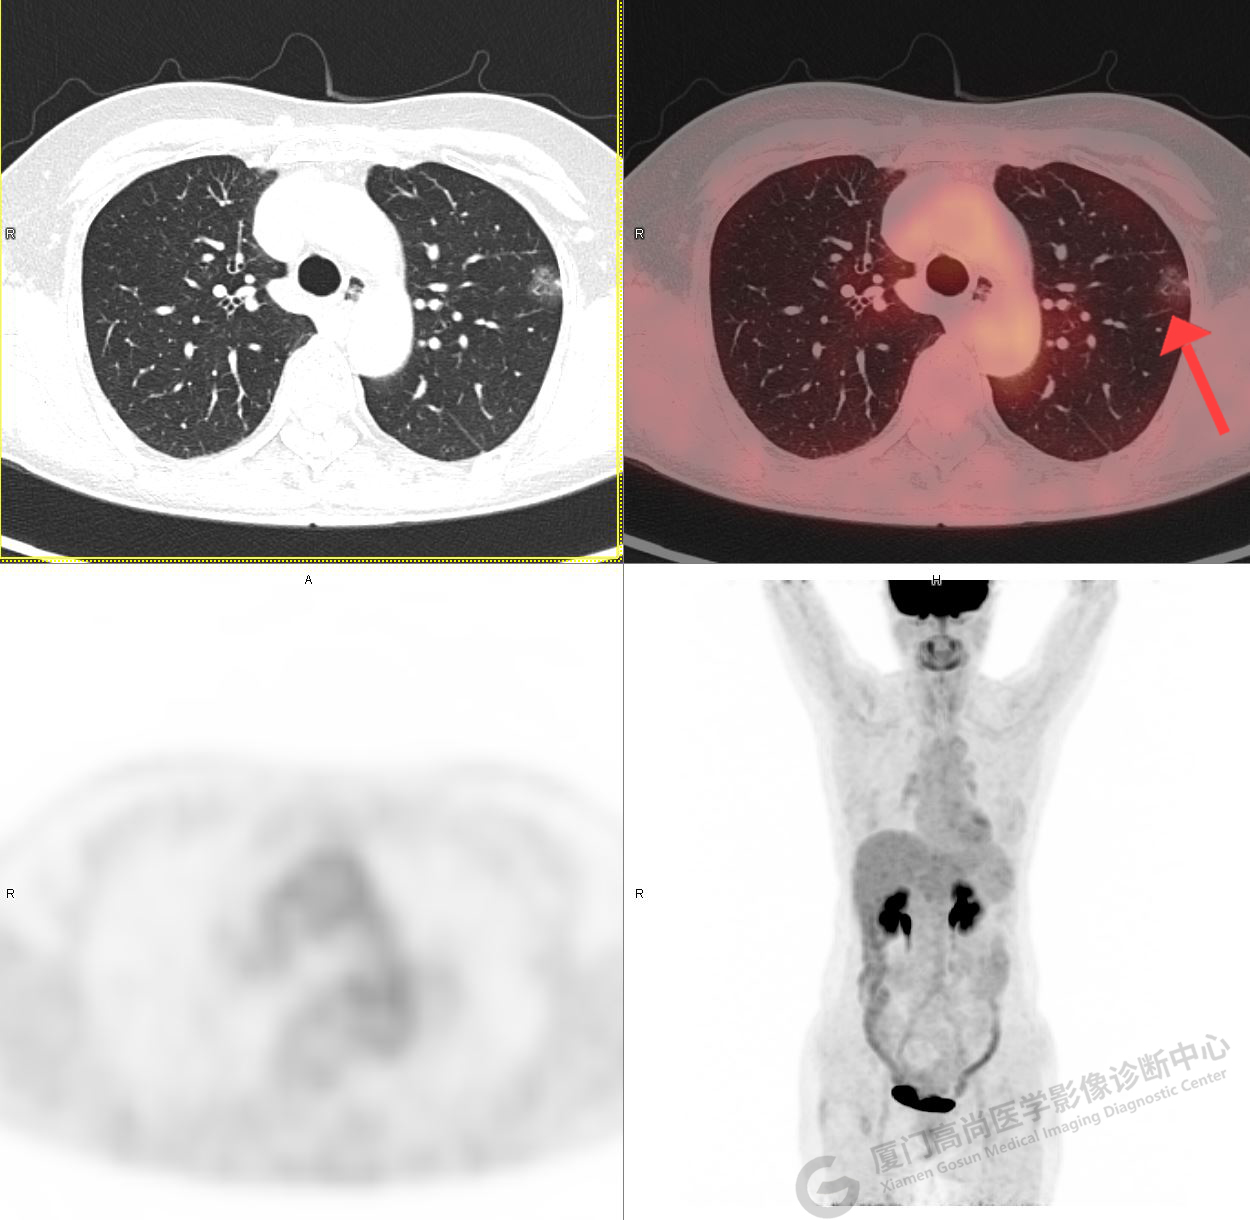

PET/CT影像圖

圖1

圖2

PET/CT示:右肺下葉結(jié)節(jié),代謝增高,考慮為周圍型肺癌,建議穿刺活檢。

病理證實(shí)是肺腺癌。